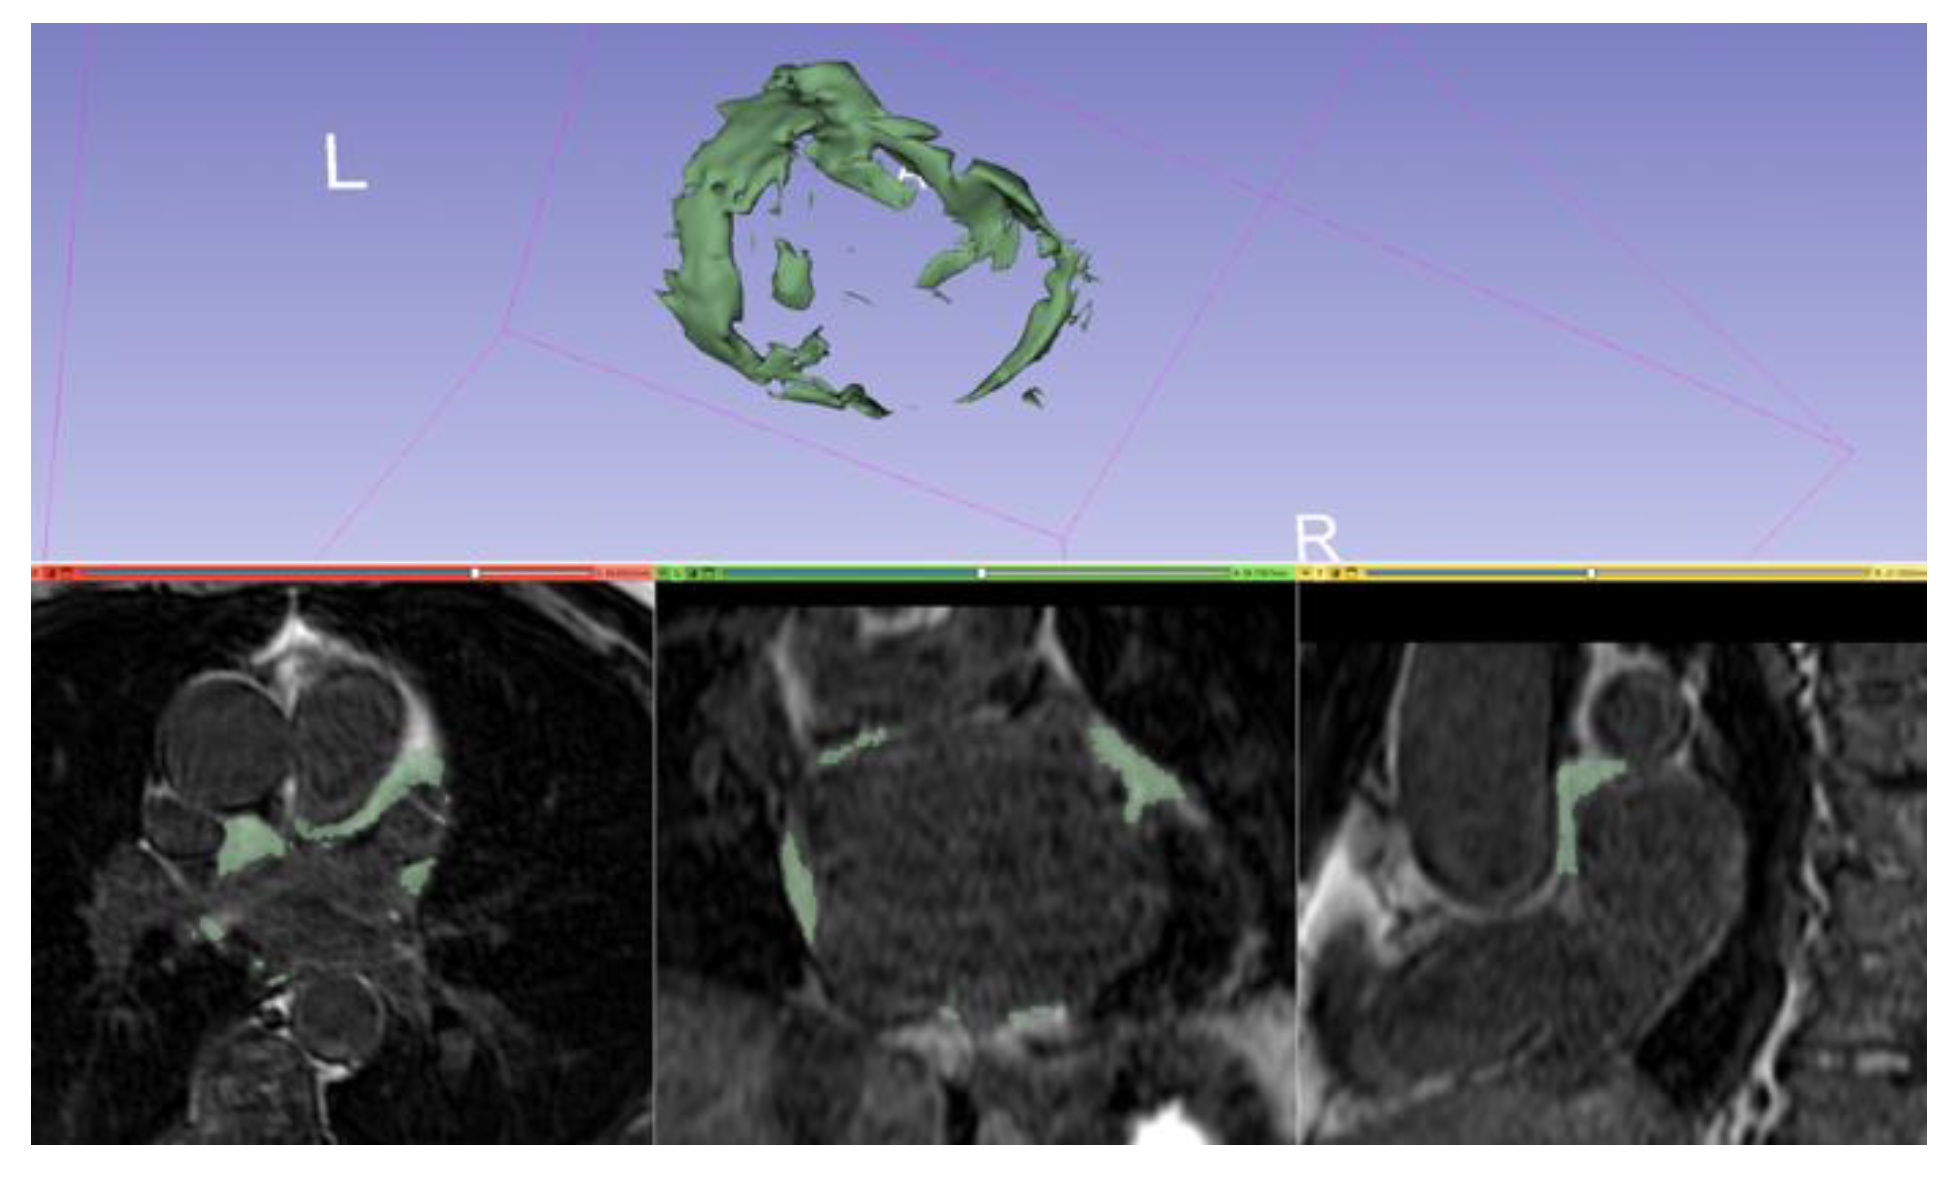

3.2. Left Atrial and Left Atrial Appendage Volume

| Cine images | bSSFP | To evaluate LA/LAA volume, ejection fraction, strain |